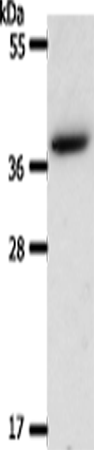

分类: 科研抗体货号: P11198别名: ARC20; P20-ARC应用: WB,IHC反应种属: Human, Mouse